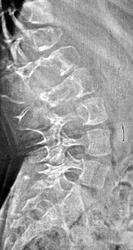

Элсберга-Дайка симптом (рентг.) - рентгенологически определяемое расширение интерпедикулярного расстояния и деформация (вогнутость) внутренних поверхностей ножек дуг. Характерен для длительно существующих объемных процессов позвоночного канала (опухоль, дермоидная киста, дермальный синус).

(С. A. Elsberg, 1871-1948, американский хирург  S. С. Dyke, совр. англ. патолог) рентгенологически определяемая деформация ножек дуг позвонков и увеличение расстояния между ножками дуг; признак опухоли спинного мозга.

При опухолях, растущих из позвоночника, и невриномах на рентгенограммах в ряде случаев обнаруживаются патологические изменения со стороны тел позвонков (остеопороз, компрессия позвонка и др.). Нередко выявляется синдром Эльсберга - Дайка, для которого характерна неправильная форма корней дужек позвонков и асимметрия расстояния между ними и остистым отростком.

Чтобы определить уровень расположения опухоли спинного мозга, применяют контрастную миелографию. Контрастным веществом служат майодил, пантопак. Производят нисходящую или восходящую миелографию. При нисходящей миелографии контрастное вещество вводят в мозжечково-мозговую цистерну: оно спускается вниз по подпаутинному пространству и задерживается на уровне верхней границы опухоли. Для восходящей миелографии применяют контрастные вещества, обладающие меньшим удельным весом, чем ликвор. Их вводят в конечную цистерну. Поднимаясь вверх, они задерживаются на уровне нижней границы опухоли.